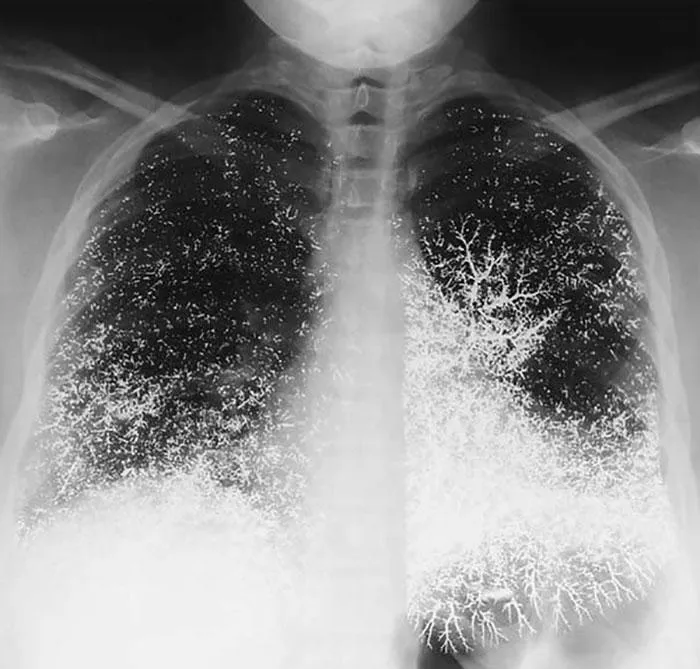

Так виглядає грудна клітина людини, як намагалась отруїтись ртуттю

Фото The New England Journal of Medicine